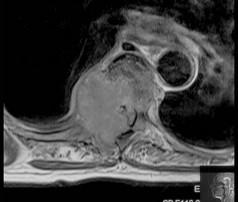

问题 女,72岁,双下肢轻度截瘫3个月余,请结合影像学检查,选出最可能的诊断 ( )

选项 A、脊柱转移瘤 B、强直性脊柱炎 C、脊椎结核 D、化脓性脊柱炎 E、椎体压缩骨折

答案 C